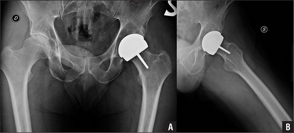

Esto, en perjuicio de pacientes que necesitan la colocación de prótesis ortopédicas sobre todo de cadera y rodilla o la utilización de algún material de osteosíntesis utilizado en traumatología para fijar huesos, como clavos, tornillos, placas, entre otros.

El número de médicos, sobre todo profesionales jóvenes y de centros públicos y privados que incursionan en la práctica de esos procedimientos, también ha ido creciendo en el país, pese a que se trata de cirugías complejas que requieren habilidades, equipamientos y quirófanos adecuados, de lo cual carecen muchos establecimientos. La prótesis debe reunir dos condiciones: estándares de calidad y diseño adaptado a la anatomía humana. Además del material, e instrumental, condiciones del quirófano y la capacidad técnica y clínica del médico.“Calidad del implante, del médico y las condiciones del lugar. Esas son las tres patas, si falla una, hay problemas.